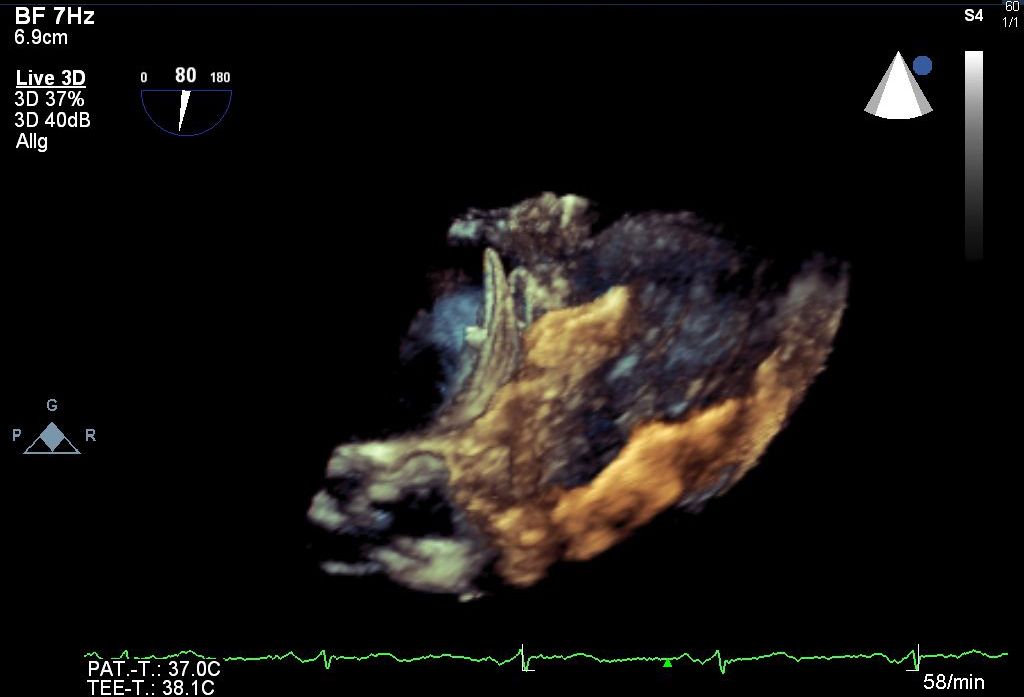

Bei Kontraindikationen für eine orale Antikoagulation, z.B. nach einer schweren Blutung,  kann das linke Vorhofohr mit einem gleichwertigen thrombembolischen Schutz vor Schlaganfällen verschlossen werden.

In unserem Herzkatheterlabor  bieten wir die Möglichkeit das linke Vorhofohr mit verschiedenen Okkludermodellen, je nach Anatomie, erfolgreich zu verschließen.